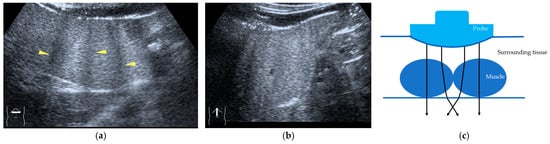

Current US machines reconstruct B-mode US images based on the assumption that sound passes through all parts of human tissues in a straight line and at a constant acoustic velocity (1540 m/s), and this assumption is applied to all scanning planes. The displayed position in a US image usually corresponds with the actual position on the structure. Strictly speaking, however, the acoustic velocity changes according to the tissues [44,45]. Thus, when a plane containing tissues with different acoustic velocities is scanned, sound refraction occurs at the interface between these tissues according to Snell’s law. As a result, the displayed position of point A (the true location) along the line that passes through the interface is falsely displayed at point A’ (a different position) in the B-mode US image as if there was no sound refraction. This refraction artifact is clearly seen in a cirrhotic liver (Figure 3), around a round mass (e.g., a hepatic cyst) (Figure 4) and below the rectus muscles in the transverse scanning plane of the upper abdomen (Figure 5). We will now provide a brief explanation for these three artifacts (Figure 3, Figure 4 and Figure 5). In macronodular liver cirrhosis, sound refraction occurs at the irregular hepatic surface, resulting in the improper positioning and display of echo brightness in the US image [44,45,46], giving the appearance of a “tricolor flag” [46] (Figure 3). When a US beam passes through a mass with an acoustic velocity different from that of the surrounding hepatic parenchyma, it changes direction twice due to sound refraction, first at the liver parenchyma–mass lesion entrance interface and again at the mass lesion–liver parenchyma exit interface. The liver structure behind the mass lesion thus appears to be deformed in B-mode US and heterogeneous in CEUS (Figure 4). As has been reported, sound refraction occurs most clearly at both edges of a mass lesion, and the degree of sound refraction is nearly proportional to the incidental angle of the US beam striking the liver parenchyma–mass lesion interface. Globally speaking, the degree of sound refraction is accentuated as the US beam strikes peripheral to the mass lesion. This is why the posterior echo behind the mass lesion is not homogeneous, as observed in Figure 4. In the transverse scanning of the upper abdomen, the US beam is largely refracted, first at the anterior wall of the rectus muscles and then at the posterior wall of the muscle (Figure 5c). As a result, the liver below the rectus muscles is more or less deformed in B-mode US and CEUS, as seen in Figure 5a,b. The most useful prevention strategy is to use the reference B-mode image (the so-called dual-image technique), which allows for a simultaneous comparison between the CEUS and B-mode images.

Figure 5.

Refraction artifact (3): hypoenhanced lines due to US refraction. (a) CEUS shows many hypoechoic lines throughout the liver parenchyma via transverse scanning (arrowheads). (b) The liver’s left lobe shows none of the lines seen in (a) via sagittal scanning. (c) A schematic drawing of sound refraction due to rectus abdominus via transverse scanning plane. The US beam changes direction twice, first at the surrounding tissue–rectus muscle interface, then at the rectus muscle–surrounding tissue interface.